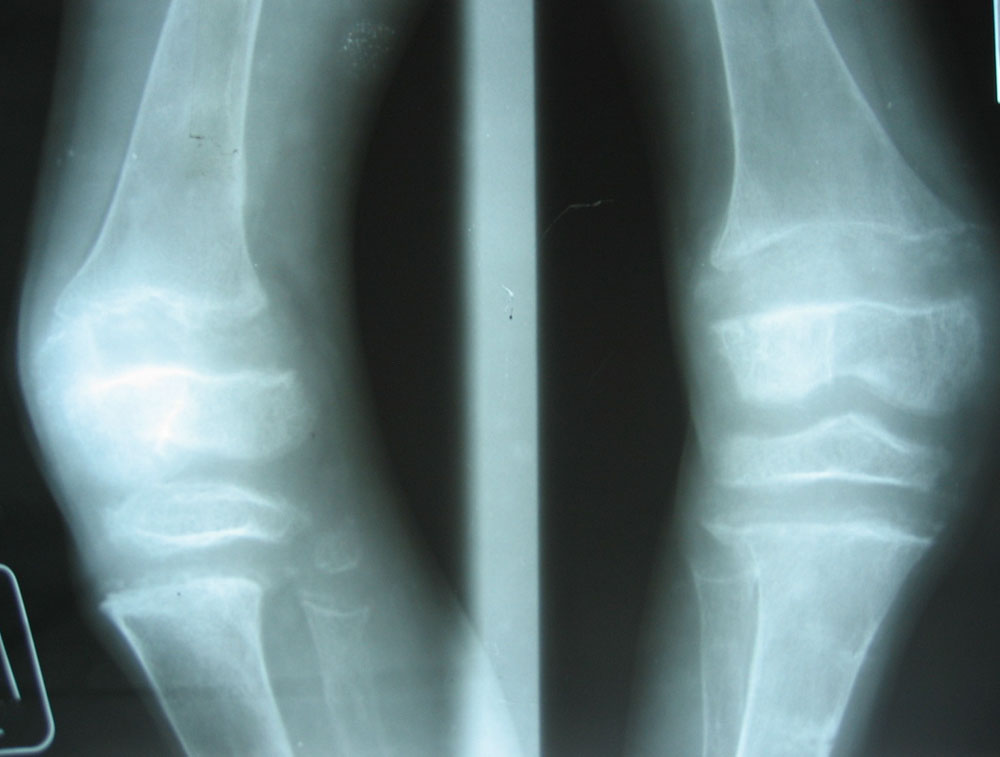

Facebook被指令兒童軟骨病人數目增加。研究員在《英國醫學雜誌》撰文指出,軟骨病是Facebook和電腦遊戲惹的禍。他們說,沉迷Facebook的青少年如變成「宅男」,長期不接觸天然日光、飲食習慣欠佳,將會導致他長期缺乏維他命D,從而患上軟骨病。